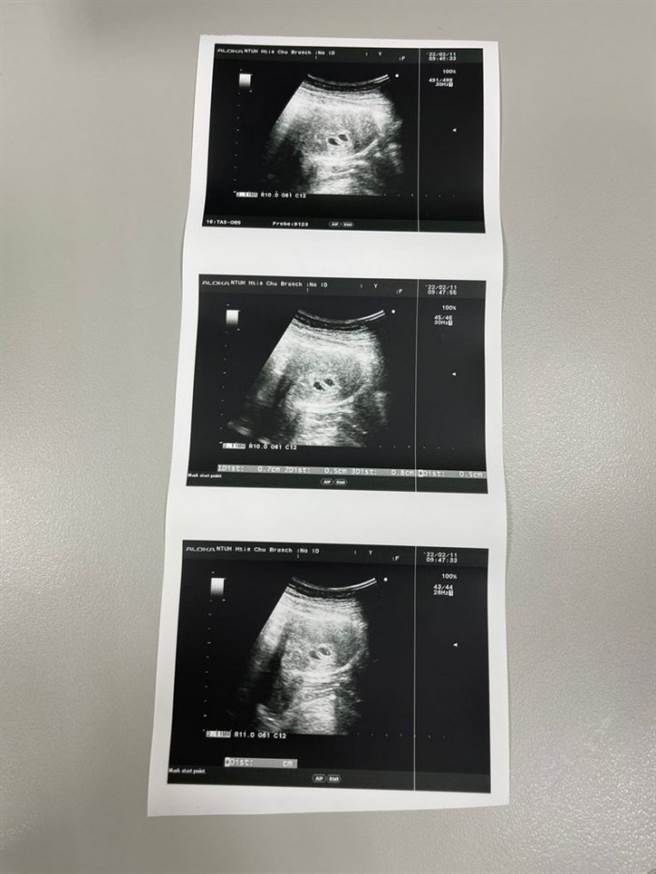

1名女网友在交友软体认识男友,某次喝醉后她让对方载去旅馆,当晚她在酒精催化下邀约发生关系,2人后来索性在一起,她后来发现意外怀了双胞胎。(翻摄自Dcard)